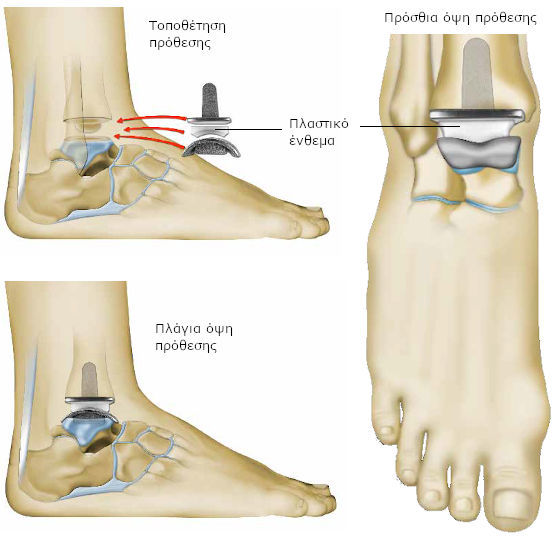

Ο χειρουργός σας αντικαθιστά την άρθρωση του αστραγάλου με πρόθεση. Στην ιατρική γλώσσα, αναφέρεται ως αρθροπλαστική ποδοκνημικής.

Ο χειρουργός προετοιμάζει το οστό της κνήμης και του αστραγάλου.

Καθαρίζει την περιοχή από τις οστικές προεξοχές (οστεόφυτα), που δημιουργήθηκαν.

Αφαιρεί, στη συνέχεια, το χόνδρο που έχει φθαρεί μαζί με χιλιοστά του οστού, που βρίσκεται από κάτω.

Οι τομές γίνονται με μεγάλη ακρίβεια, ώστε να ταιριάζουν τέλεια με το μέγεθος της πρόθεσης.

Ο χειρουργός, στη συνέχεια, τοποθετεί δοκιμαστική πρόθεση, για να δοκιμάσει τις διάφορες κινήσεις της άρθρωσης.

Μπορεί να χρειαστούν, κάποιες διορθωτικές κινήσεις πριν την τοποθέτηση της τελικής πρόθεσης.

Το τμήμα, που τοποθετείται στην κνήμη περιλαμβάνει ένα είδος μικρού στελέχους. Η άλλη του άκρη είναι επίπεδη και οριζόντια.

Το τμήμα της πρόθεσης, που εισάγεται στον αστράγαλο μπορεί να στερεωθεί με τη χρήση βιδών ή ενός είδους μικρών βελόνων. Το σχήμα του είναι ανάλογο του φυσικού αστραγάλου.

Ανάμεσα σε αυτά τα δύο μεταλλικά τμήματα, ο χειρουργός τοποθετεί ένα πλαστικό τμήμα (ένθεμα). Αναπαράγονται ακριβώς οι φυσιολογικές κινήσεις της άρθρωσης.

Συνδυαστικές επεμβάσεις

Πριν την τοποθέτηση της τελικής πρόθεσης, ο χειρουργός μπορεί να προβεί σε επιπλέον βελτιωτικές ενέργειες. Οι ενέργειες αυτές αποσκοπούν, είτε στην καλύτερη συγκράτηση της πρόθεσης, είτε στη βελτίωση του βαδίσματος.